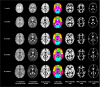

UNC detail-preserved longitudinal 0-3-6-9-12 months-old atlas

Zhang, Y., Shi, F., Wu, G., Wang, L., Yap, P.T. and Shen, D., 2016. Consistent spatial-temporal longitudinal atlas construction for developing infant brains. IEEE transactions on medical imaging, 35(12), pp.2568-2577.